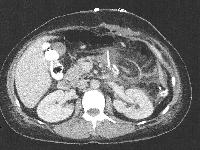

Πρόκειται για γυναίκα ασθενή 43 ετών, η οποία υποβλήθηκε σε υπερηχογράφημα άνω κοιλίας στα πλαίσια διερεύνησης άτυπων γαστρεντερικών συμπτωμάτων (αίσθημα κορεσμού και τάση προς έμετο). Διαπιστώθηκε η ύπαρξη ευμέγεθους μάζας της παγκρεατικής ουράς, διαμέτρου 22 cm, με κυστικά και συμπαγή στοιχεία. Η αξονική τομογραφία επιβεβαίωσε τα υπερηχογραφικά ευρήματα (εικόνα 1) και επιπλέον ανέδειξε το γεγονός ότι η μάζα εκτείνονταν ως το σπλήνα, ενέπλεκε το στόμαχο, τον αριστερό νεφρό, το μεσεντέριο και το παχύ έντερο και ότι έφτανε ως τα οστά της πυέλου (εικόνα 2). Εγχειρητικά, ύστερα από πολύωρη παρασκευή, η μάζα αποκολήθηκε en block από όλες τις προαναφερόμενες ανατομικές δομές (εικόνα 3) και, ύστερα από διαίρεση του παγκρεατικού παρεγχύματος στο επίπεδο του αυχένα του οργάνου, απομακρύνθηκε από το χειρουργικό πεδίο μαζί με το σπλήνα (εικόνα 4). Η ιστοπαθολογική εκτίμηση του παρασκευάσματος (εικόνα 5) ανέδειξε συμπαγή ψευδοθηλώδη όγκο, χωρίς στοιχεία κακοήθειας. Η άμεση μετεγχειρητική πορεία ήταν ανεπίπλεκτη, χωρίς την ανάπτυξη ενδοκοιλιακών συλλογών (εικόνα 6). Η ασθενής έλαβε εξιτήριο την 8η μετεγχειρητική ημέρα.